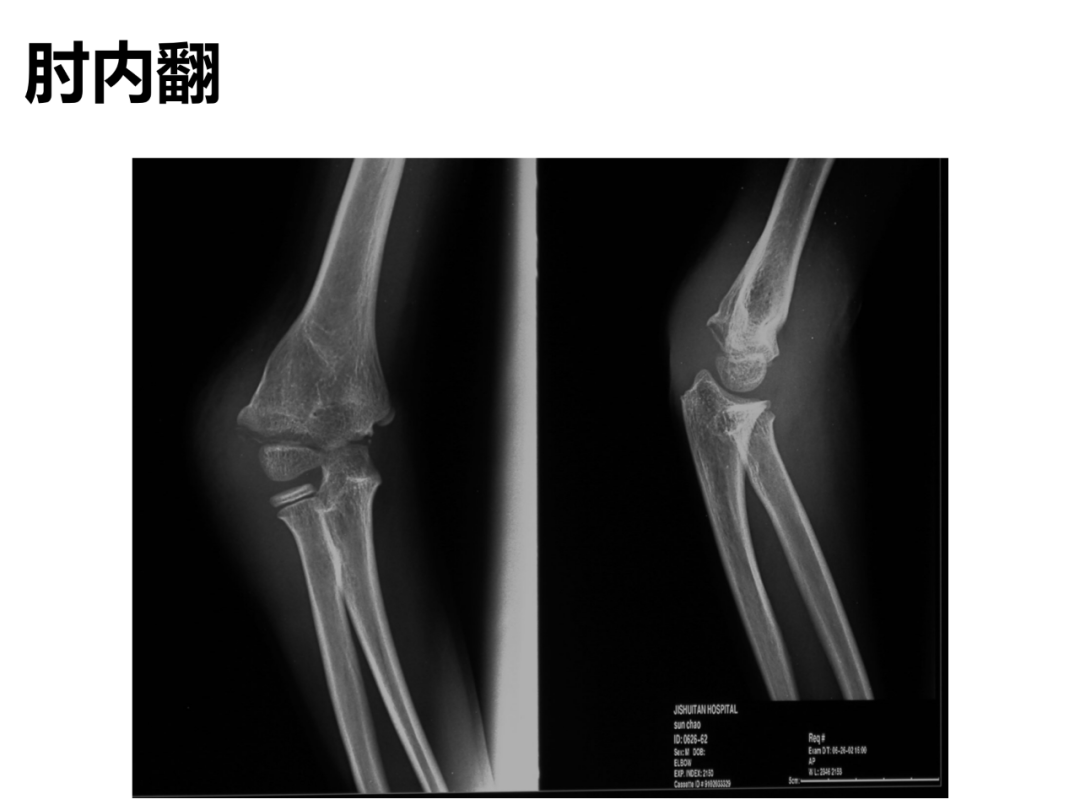

小儿骨科X线片汇总,临床读片宝典!